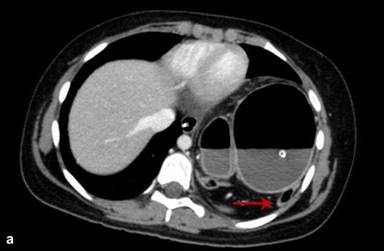

Laboratory investigations showed the patient to be anaemic (Hb 9 gm%) with leucocytosis (16,000/cubic mm) and a predominance of polymorphonuclear cells (80%). Scanogram revealed a dilated stomach with inverse orientation as evidenced by the position of the Ryle’s tube (Figure 1). A screening abdominal ultrasound failed to demonstrate the spleen in the left hypochondrium. The spleen was present in the umbilical region and extended into the left lumbar region. The bowel loops occupied the left upper quadrant. A contrast enhanced computed tomography (CECT scan) of the chest and abdomen was performed. It depicted a grossly distended stomach with the fundus lying in the left hemi-thorax and an air-fluid level within (Figure 2). The pylorus lay close but a little above the gastro-oesophageal junction, a finding consistent with gastric volvulus (Figure 3). There were no accompanying signs of gastric infarction. An enlarged spleen was visualised occupying the umbilical and the left lumbar region, extending along the undersurface of the left lobe of the liver and reaching below the lower pole of the left kidney (Figures 4, 5). The splenic pedicle had undergone torsion with consequent volvulus of pancreatic tissue. The splenic parenchyma however, had a homogenous attenuation, thus excluding any splenic ischemia. The pancreas was seen compressed between the stomach and the spleen (Figures 3, 5). A diagnosis of pancreatic volvulus due to torsion of wandering spleen, diaphragmatic hernia with an intra-thoracic gastric volvulus and resultant gastric outlet obstruction was thus established.

Figure 2. Axial CT scan chest, mediastinal (a.) and lung (b.) window, demonstrate a grossly distended stomach in the left hemithorax with an air fluid level within. Note the accompanying mesentery and bowel in the herniated segment (red arrow). |